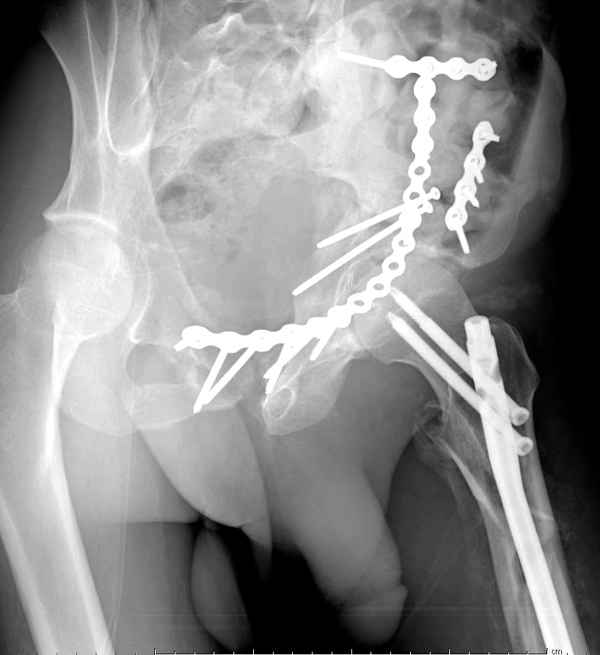

Здесь несколько вариантов двухколонных свежих переломов, которые были оперированы из одного-заднего, а также из двух: переднего и заднего доступов.

Имя     : 1 Both column one incision.jpg

Тип     : image/jpeg

Размер  : 25084 байтов

Url     : http://weborto.net:8080/pipermail/ortho/attachments/20100506/5c268106/attachment-0010.jpg

Имя     : 1 Bothcolumn.jpg

Размер  : 33886 байтов

Url     : http://weborto.net:8080/pipermail/ortho/attachments/20100506/5c268106/attachment-0011.jpg